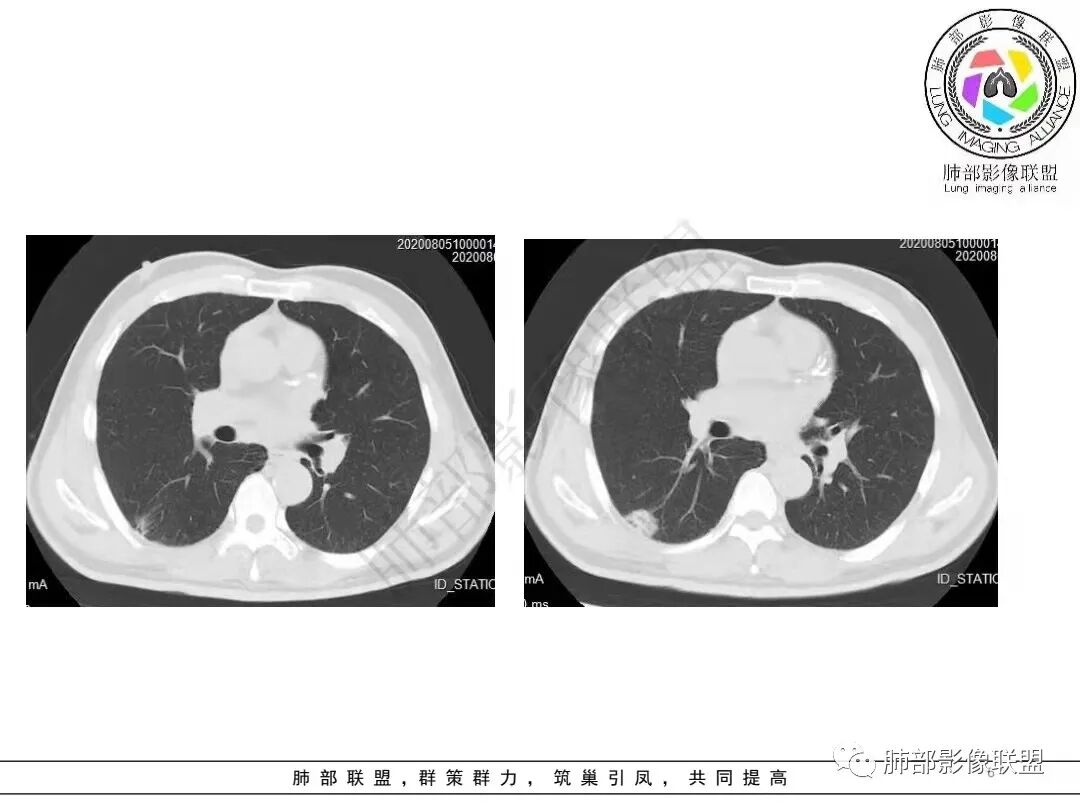

2.病例二:30岁女性,发现病灶6个月前有咳嗽咳痰及治疗史,肿瘤标志物阴性。左肺下叶胸膜下结节影,整体较膨隆,局部边缘较平直,可见毛刺,同样可见磨玻璃密度区,病灶内可见空泡征,周围可见细小毛刺及多发棘突影,同样外围病灶支气管情况难以判断。邻近肺组织内可见多发微小结节影。病灶张力不高,未见分叶及胸膜牵拉,由于纵隔窗图像太少,不宜判断胸膜下脂肪间隙有无受累,可疑胸膜下有微量积液。